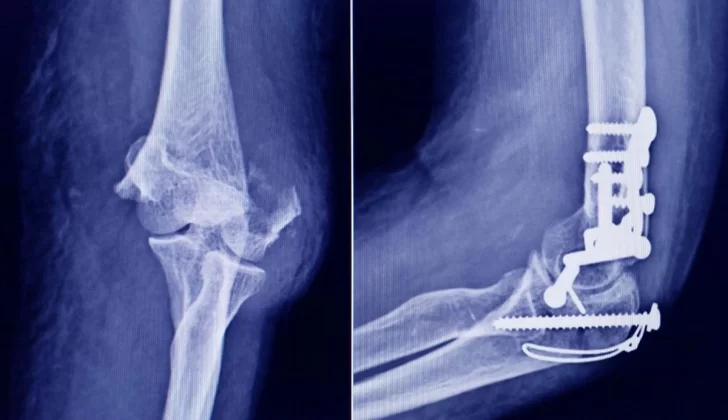

La Administración Nacional de Medicamentos, Alimentos y Tecnología Médica (ANMAT) advirtió a la población por un tornillo utilizado en cirugías traumatológicas debido a que es falso, por lo que su uso representa riesgo para la salud del paciente al que se lo implante.

Se trata de un tornillo utilizado en cirugías traumatológicas que fue detectado durante una inspección de control de mercado realizada en una ortopedia ubicada en la ciudad de San Miguel de Tucumán.

Dicho tornillo es producido por la firma Stryker Corporation, que se encuentra registrada ante ANMAT bajo el PM 594-139. Luego de la inspección, se exhibió la muestra recolectada ante la responsable técnica de dicha empresa, quien afirmó que se trataba de un producto falsificado.

Al tratarse de un producto falsificado, se desconoce el origen, composición, seguridad y aptitud del producto mencionado, por lo que su uso representa riesgo para la salud del paciente a quien se lo implante.